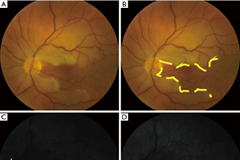

急性视网膜动脉缺血

急性视网膜动脉缺血包括单眼一过性视力丧失(TMVL)、视网膜分支动脉阻塞(BRAO)、视网膜中央动脉阻塞(CRAO)和眼...

Michael Dattilo, Nancy J. Newman, Valérie Biousse